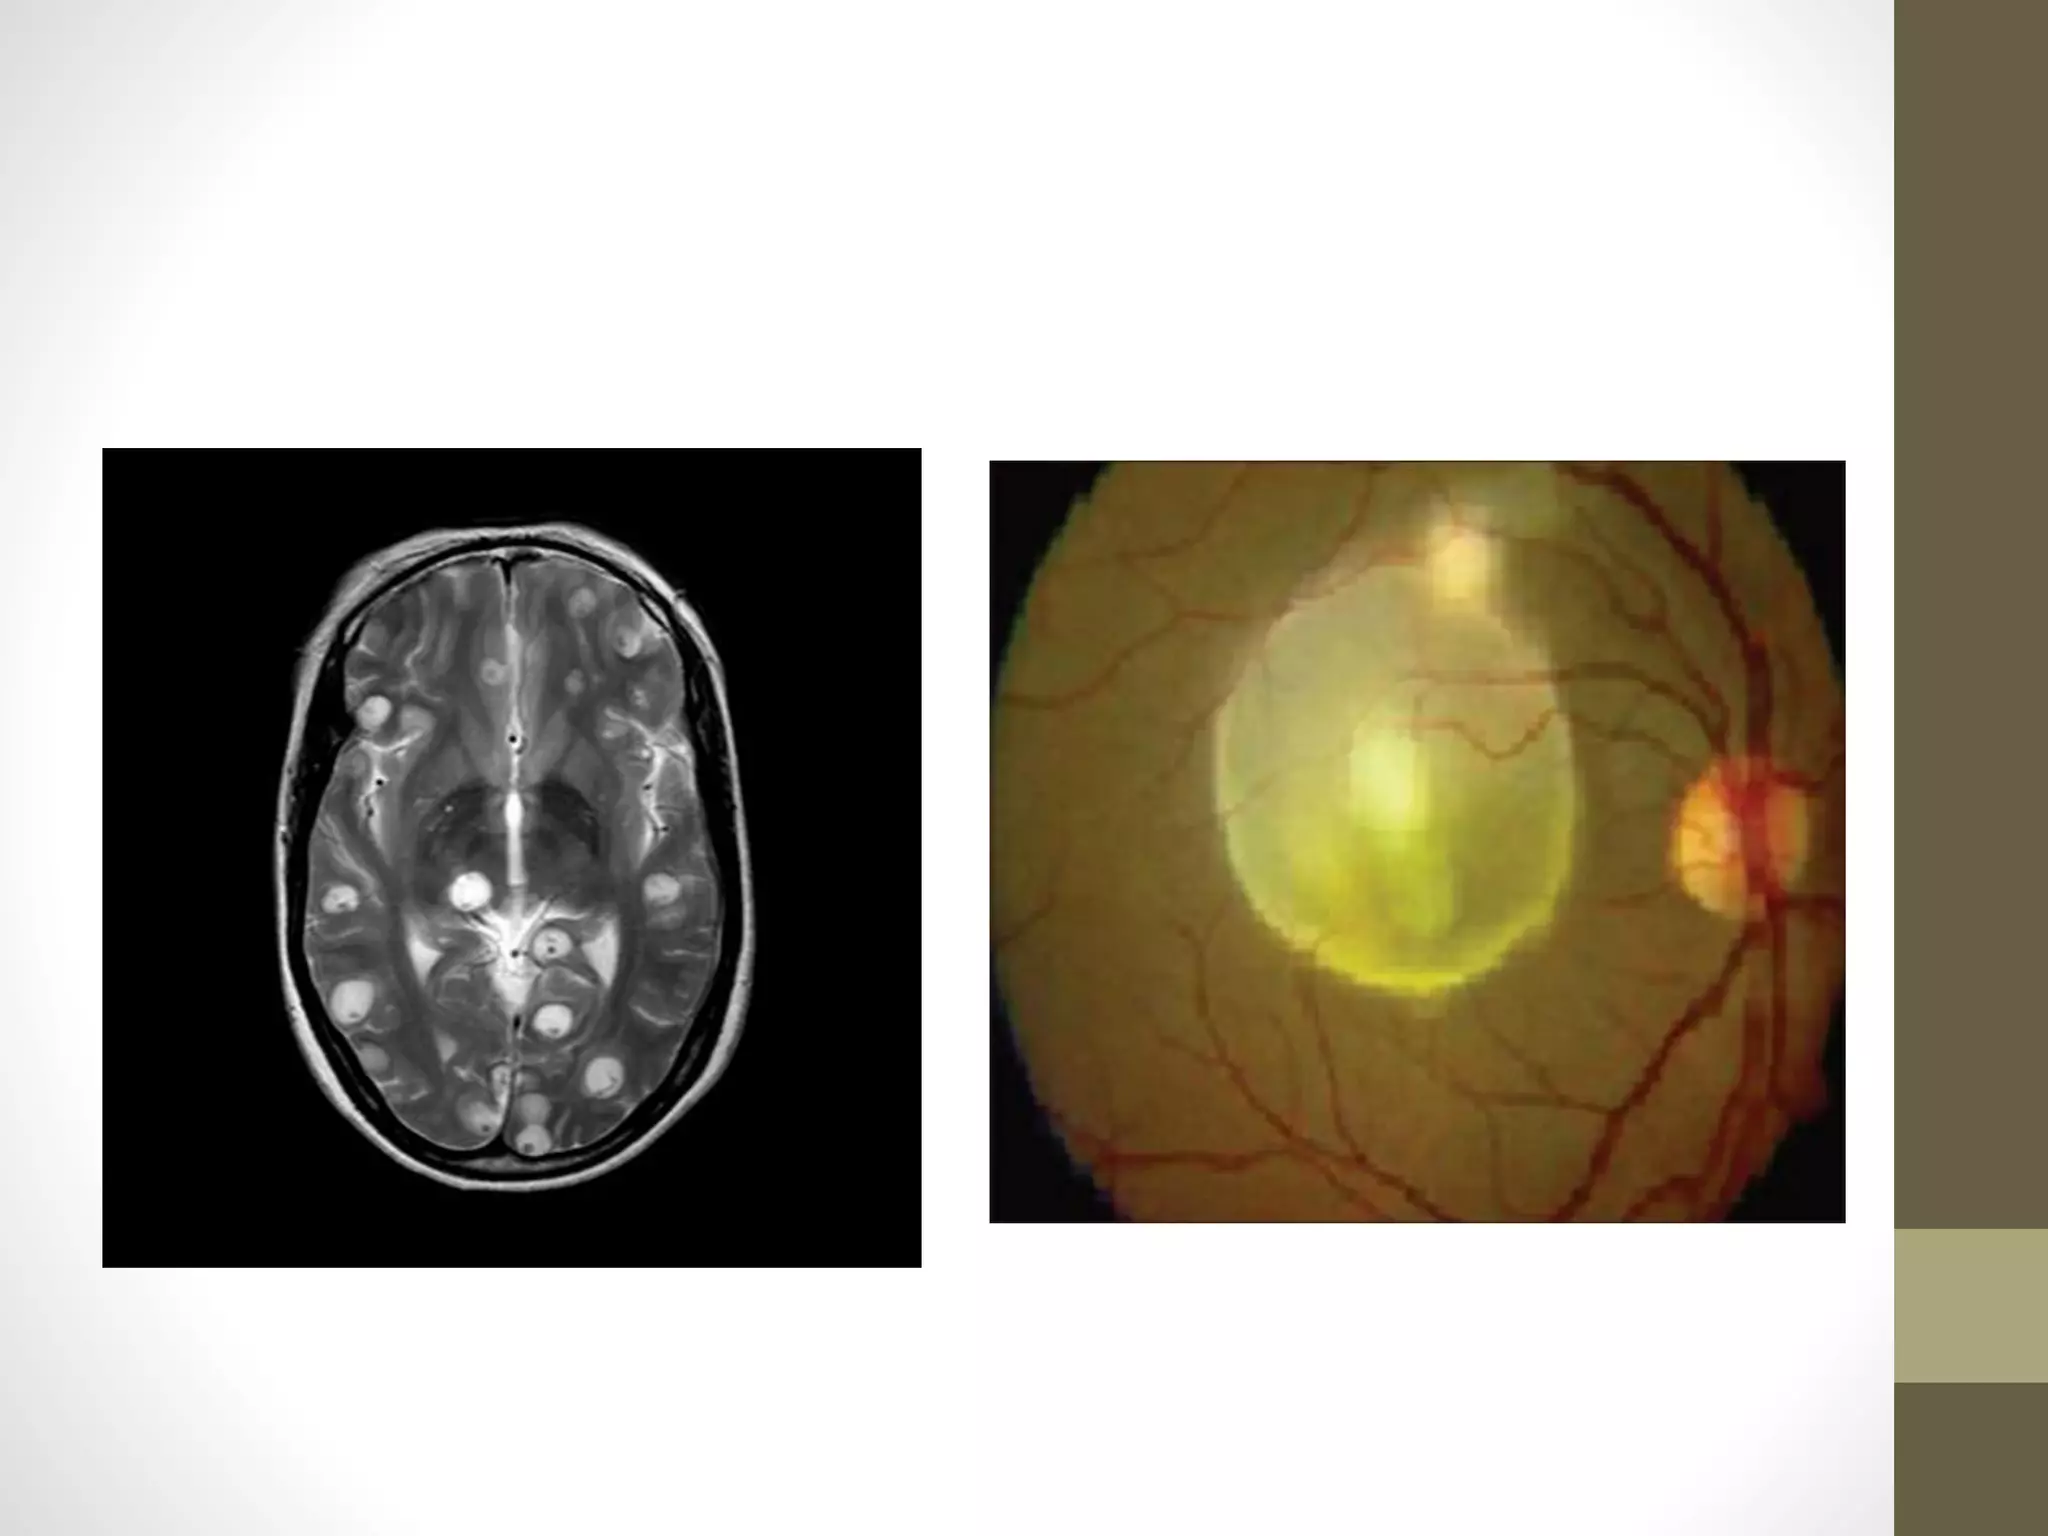

Systemic disease may involve the lungs, muscle and CNS

MRI and CT imaging are effective at

demonstrating cysts; plain X-rays may show calcified cysts.

Ocular features include cysts of the conjunctiva and

occasionally the orbit and eyelids.

The anterior chamber may show a free-floating cyst .

Larvae entering the subretinal space can cause exudative retinal

detachment

They can also pass into the vitreous where released toxins can

incite an intense vision-threatening inflammatory reaction.